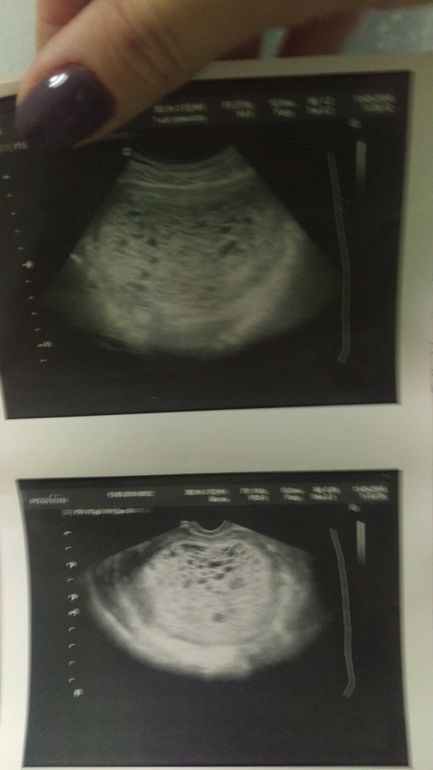

Медицина и диагностика: Инвазивный пузырный занос на УЗИ

Раздел: Альбом идей